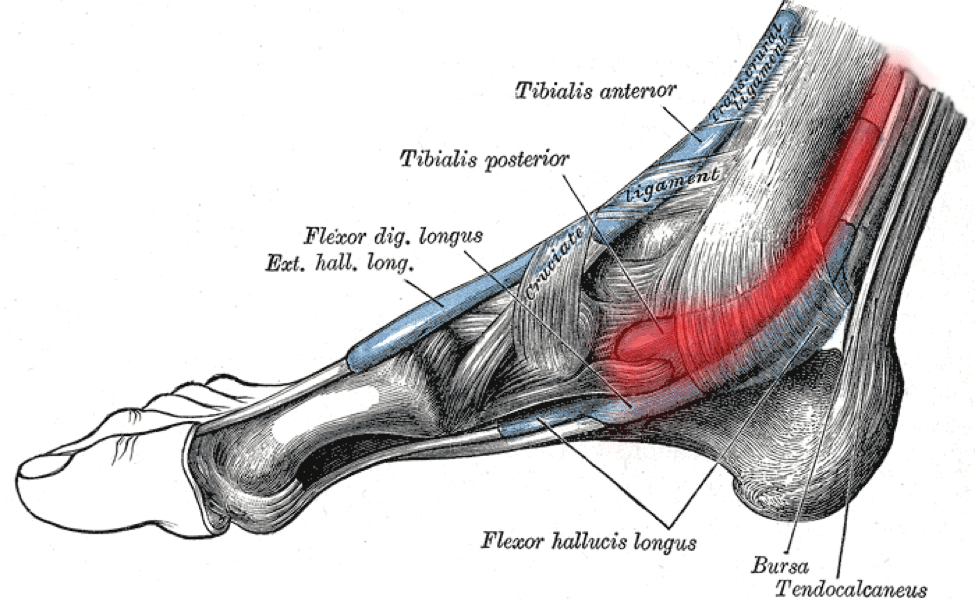

Posterior Tibial Tendonitis Signs and Treatment

Inside Ankle Pain Medial Symptoms Causes Treatment Rehab

Inside Ankle Pain Medial Symptoms Causes Treatment Rehab

Tarsal Tunnel Syndrome

Running with Pain on the Inside of the Ankle Physiotherapy